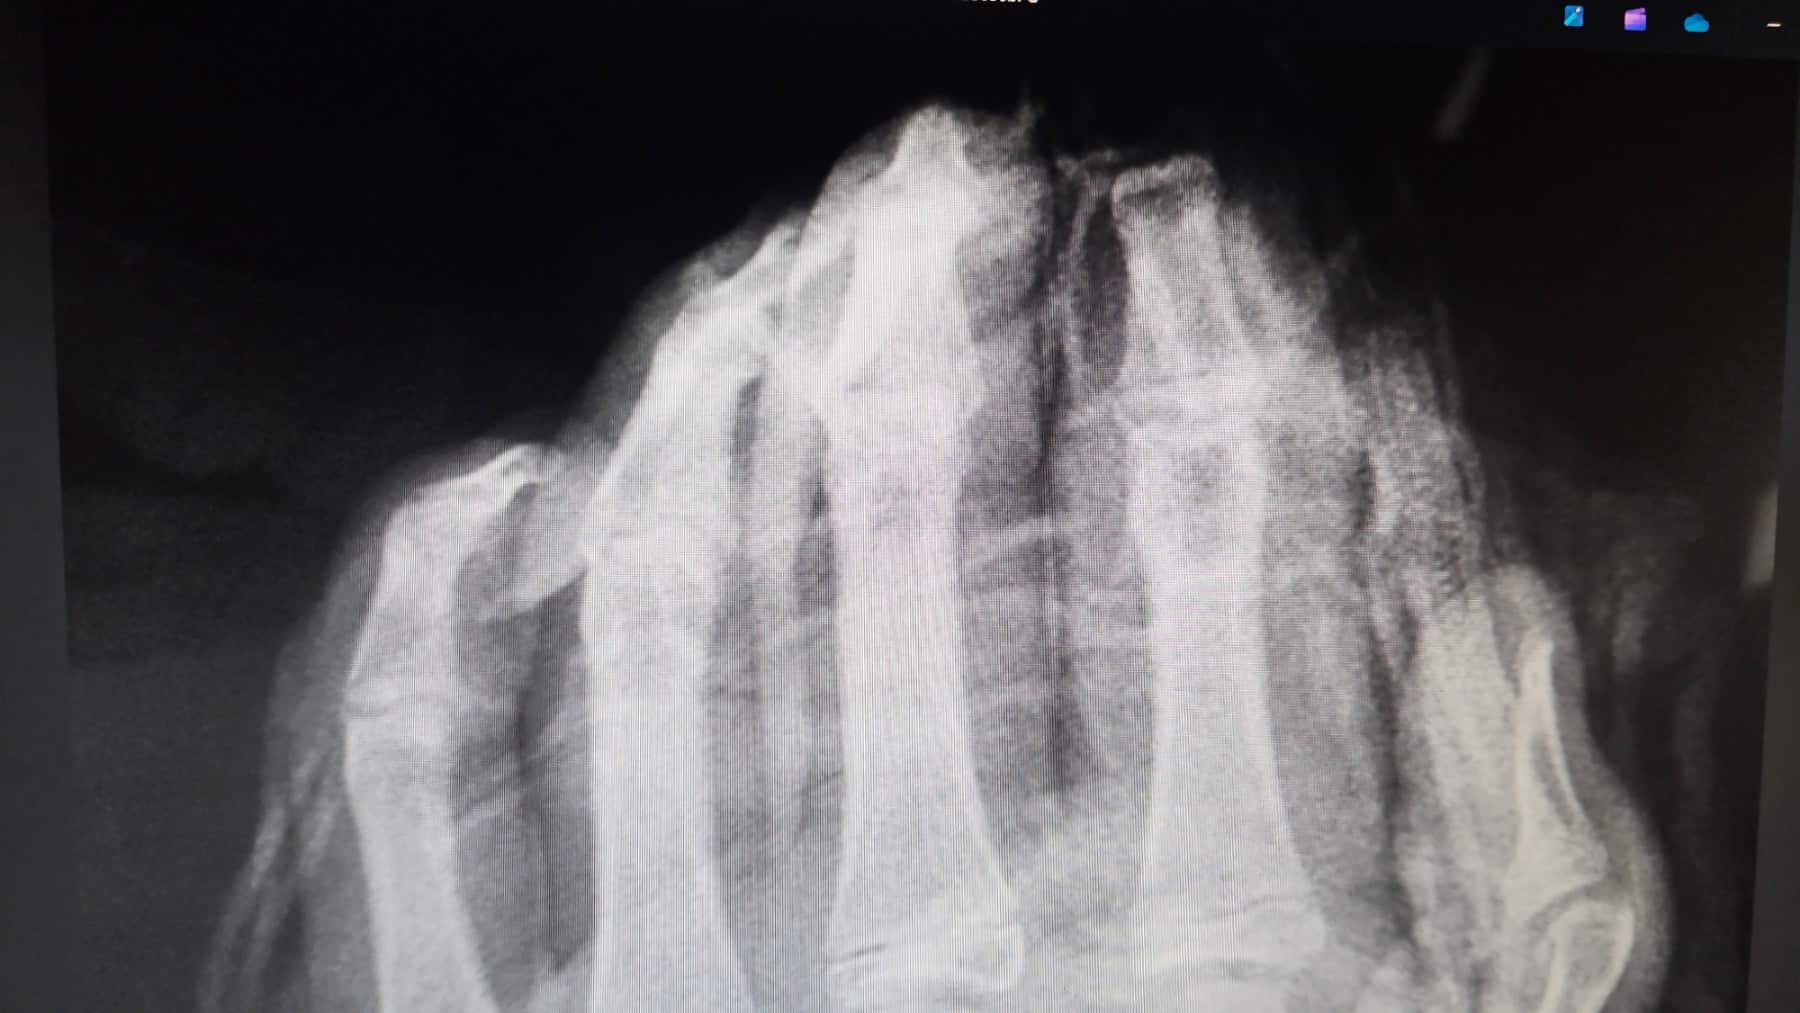

Andrej Strahovnik, dr. med., specialist kirurg iz Splošne bolnišnice Celje je spregovoril o nesrečah povzročenih s pirotehničnimi sredstvi. Povedal je , da so v tretjini vseh primerov poškodovane roke, sledi obraz, obrazni del ter poškodbe sluha in vida. V večini primerov gre za trajne posledice, saj eksplozija povzroči raztrganine, zmečkanine mikroembolije drobnih žil, poškodbe živcev in obsežne poškodbe mehkih tkiv, zato je potreben pri oskrbi tovrstnih poškodb multidisciplinaren pristop različnih vrst specialnosti. Poudaril je, da tudi najboljša kirurška tehnika včasih ne zmore popravit vsega, kar naredi drobec sekunde pri raztrganinah. Posebej zahtevna je tudi rehabilitacija. Največ poškodovancev je starih od 20 do 30 let, sledijo najstnik. Kar v 80 % gre za poškodovance v delovni dobi, kar jim precej spremeni ekonomski status. Povedal je še, da gre za poškodbe, ki jih je možno preprečiti z neuporabo in ne nakupom pirotehnike.

Ranko Lazarevič, 20 letni fant s Koroške, se je novembra lani hudo poškodoval pri uporabi pirotehnike. Pirotehnično sredstvo, za katerega je kasneje izvedel, da ni bilo kupljeno v trgovini, ampak izdelano doma, mu je odtrgalo desno roko, od zapestja. Ranko, ki je bil desničar se je po poškodbi začel učiti hranjenja, pisanja, oblačenja z levo roko. Na srečo je velik borec in optimist. Veseli se proteze, ki bi jo naj dobil še letos in zelo se veseli, da se bo s pomočjo proteze, čez nekaj časa znova vrnil v službo. Pok pirotehnike ga še vedno močno pretrese in misli odnese v trenutke groze. Vsem mladim polaga na srce, naj ne uporabljajo pirotehnike.